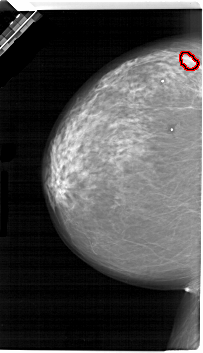

A_1657_1.LEFT_CC

FILE: A_1657_1.LEFT_CC.OVERLAY

TOTAL_ABNORMALITIES 1

ABNORMALITY 1

LESION_TYPE MASS SHAPE LOBULATED MARGINS OBSCURED

ASSESSMENT 4

SUBTLETY 3

PATHOLOGY MALIGNANT

TOTAL_OUTLINES 1

BOUNDARY